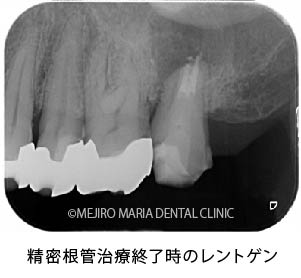

歯根端切除術(意図的再植術)から3週間後の経過観察で、瘻孔の消失が確認できました。また、術後3ヶ月経つと、根尖部付近に確認できていた根尖性歯周炎も小さくなりました。患者様も「噛んだときにも、違和感や痛みなどはない」ということで、予後は良好だと判断しました。今後は最終補綴処置を行う予定です。

今回の症例の患者様は、病変が大きいことから、かかりつけ医に抜歯を宣告されて、当院へ相談に来られました。当院の治療により、瘻孔(フィステル)は消失し、歯根端切除術(意図的再植術)3ヶ月後の経過観察では、明らかな病変の縮小が確認されました。